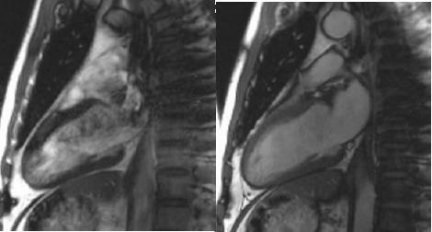

6. Click Scan and view the results.

• The image improvements are demonstrated in all gated 2D FIESTA scans.

Figure 6. Reduced susceptibility artifact (right image)

Figure 7. Off-resonance artifact at 3.0T (left) and reduced artifact (right)